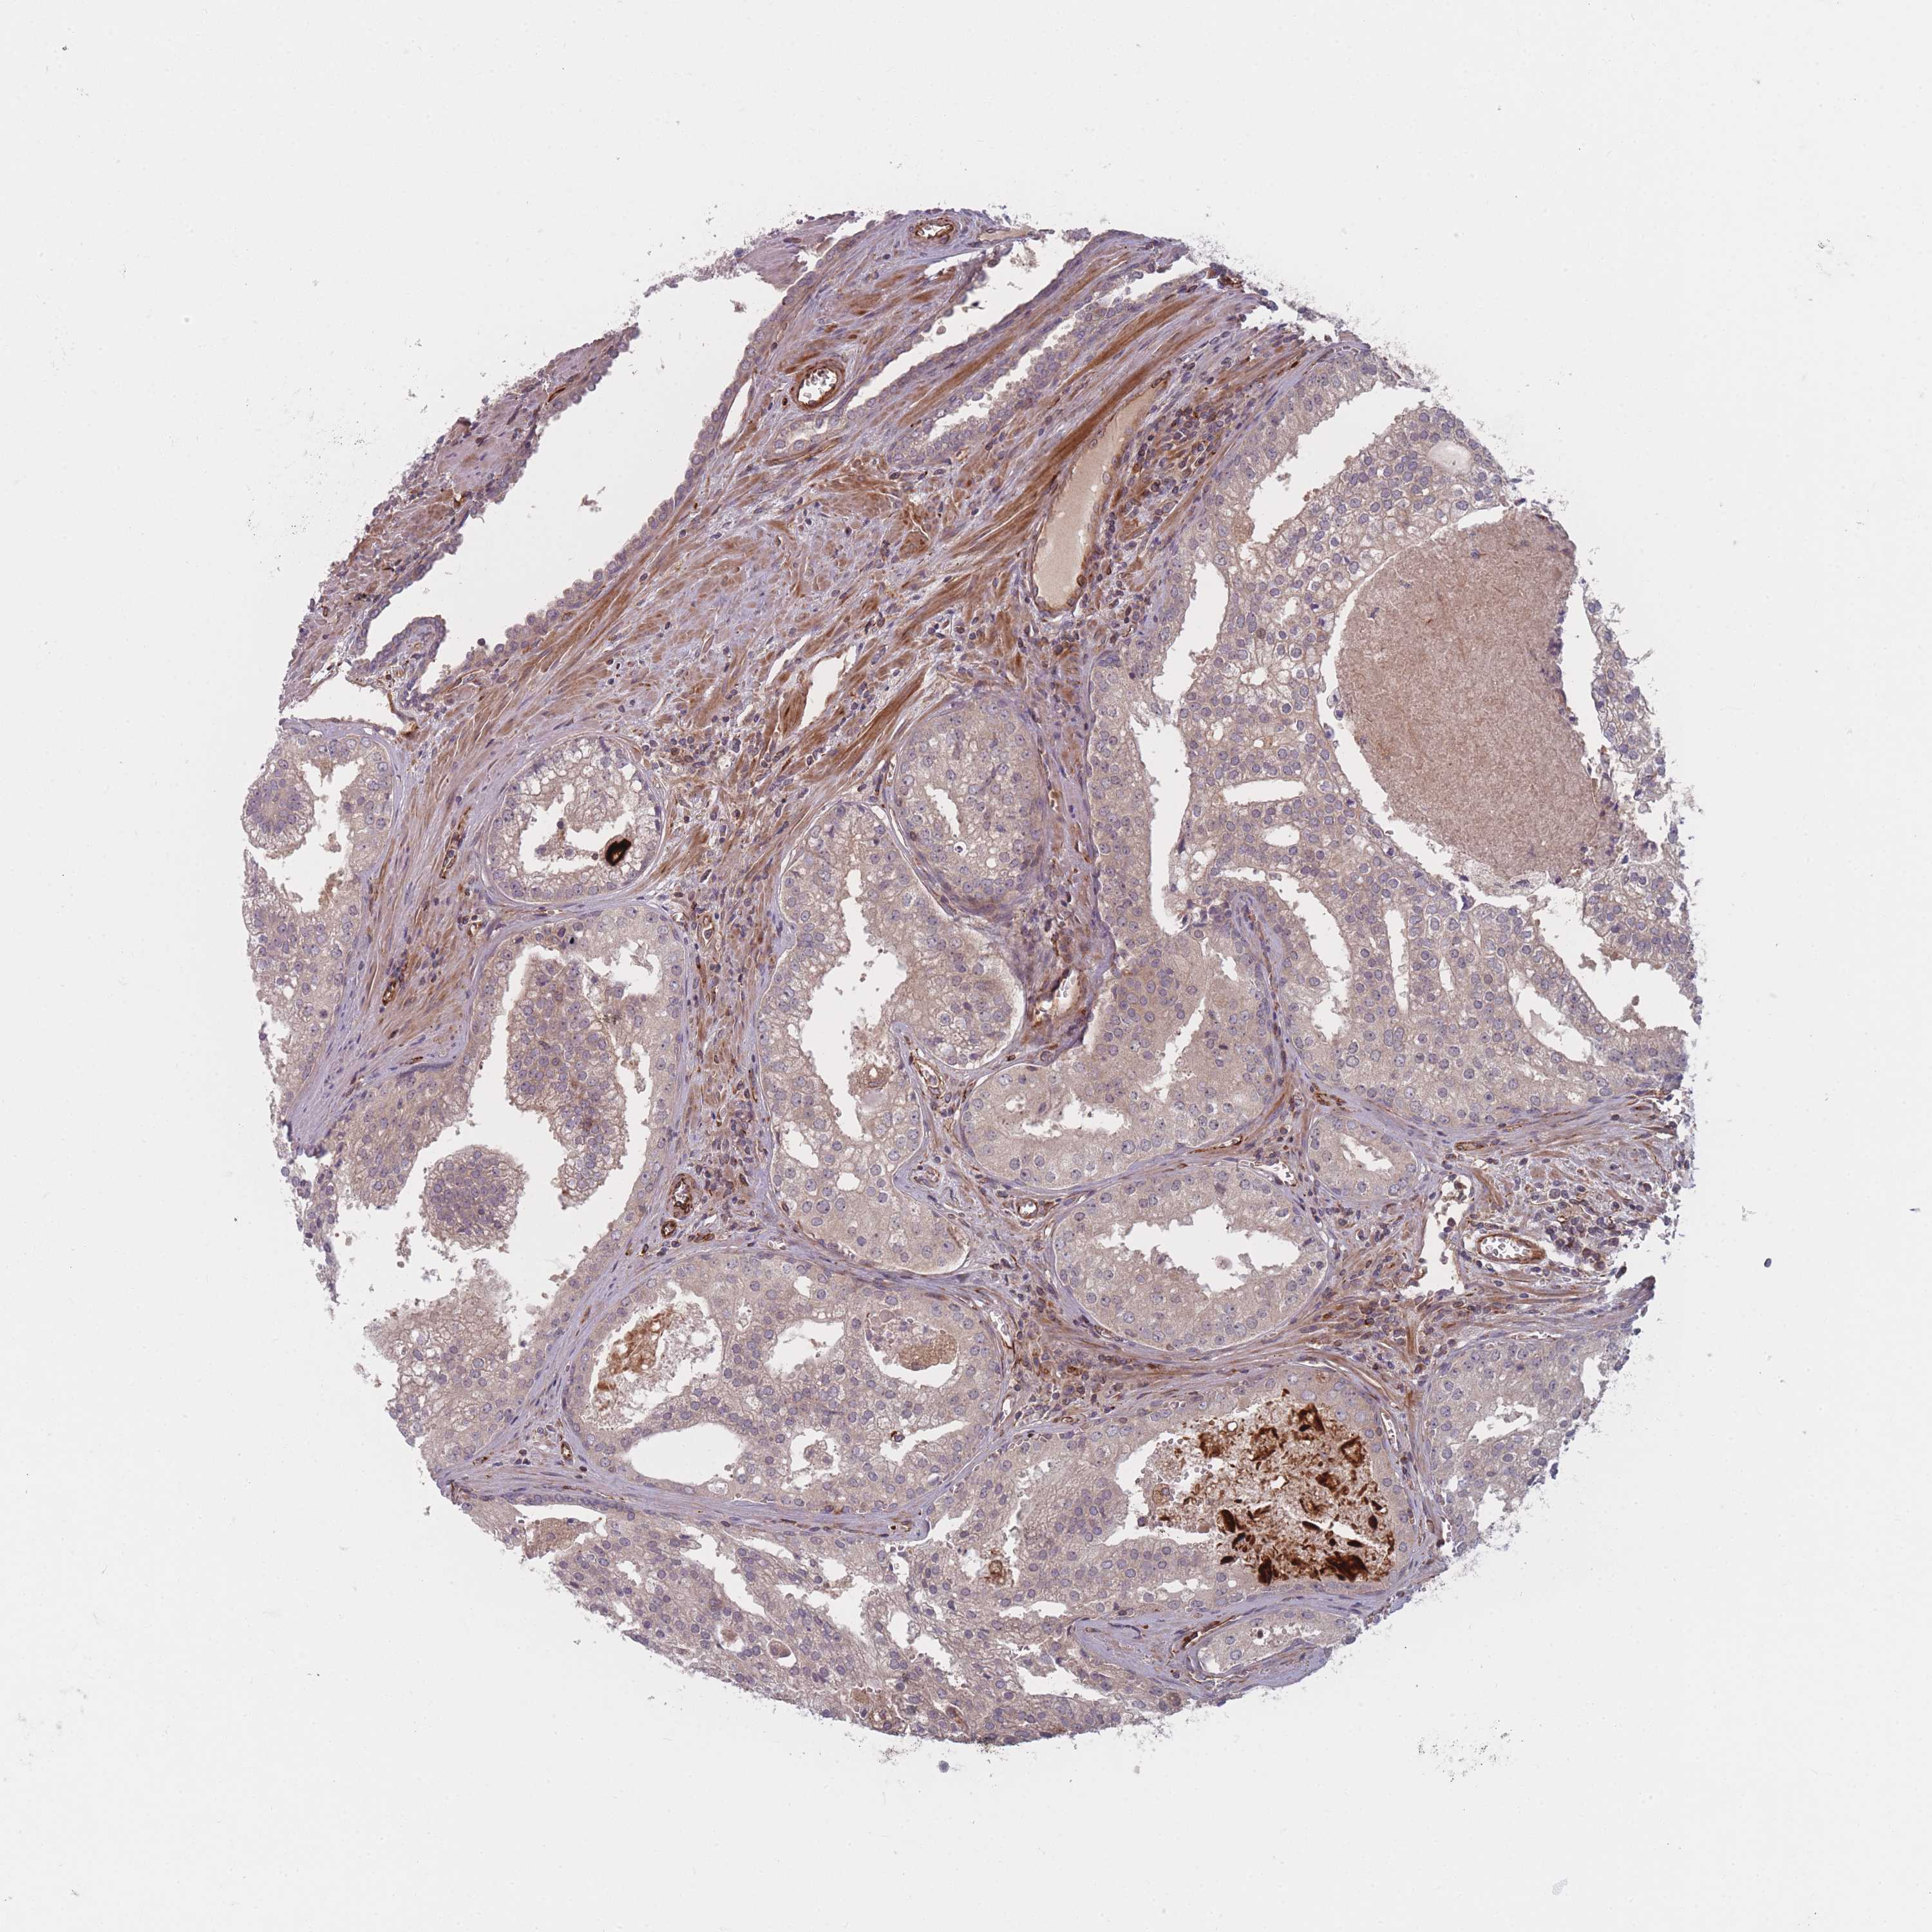

PROSTATE CANCER - Protein expressioni

A mouse-over function shows sample information and annotation data. Click on an image to view it in a full screen mode. Samples can be filtered based on level of antibody staining by selecting one or several of the following categories: high, medium, low and not detected. The assay and annotation is described here.

Note that samples used for immunohistochemistry by the Human Protein Atlas do not correspond to samples in the TCGA dataset.

Antibody stainingi

Antibody staining in the annotated cell types in the current human tissue is reported as not detected, low, medium, or high, based on conventional immunohistochemistry profiling in selected tissues. This score is based on the combination of the staining intensity and fraction of stained cells.

Each image is clickable and will lead to virtual microscopy that enables deeper exploration of all samples and also displays staining intensity scores, fraction scores and subcellular localization as well as patient and tissue information for each sample.

Antibody HPA050138

Staining

High

Medium

Low

Not detected

Intensity

Strong

Moderate

Weak

Negative

Quantity

>75%

75%-25%

<25%

None

Location

Nuclear

Cytoplasmic/membranous

Cytoplasmic/membranous,nuclear

Adenocarcinoma, High grade

Adenocarcinoma, Low grade